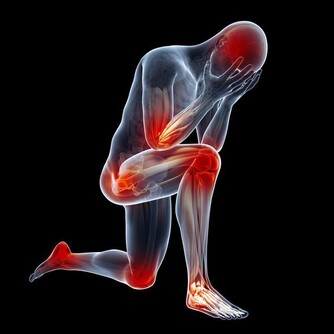

胸悶難受,試試按摩這裡

今天,小編就教大家幾種按摩穴位的方法來緩解這種症狀。